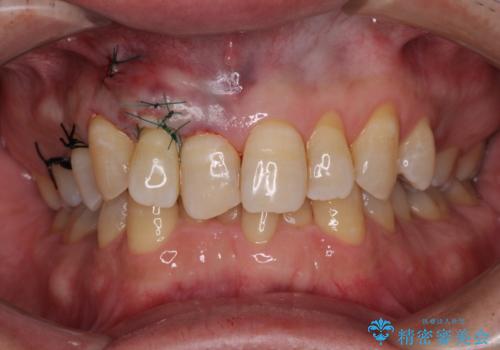

口蓋(上顎の内側)から採取した結合組織(歯肉の内側の組織)を移植することによる、根面被覆術を行うこととしました。

ディープバイトで咬合力が強く、該当歯に負担のかかりやすい咬み合わせであったため、歯肉退縮が起こりやすいと判断された患者様でした。

根面被覆を達成するとともに、歯肉の厚みを増すことで、今後歯肉退縮を起こしにくくするよう配慮した処置としました。